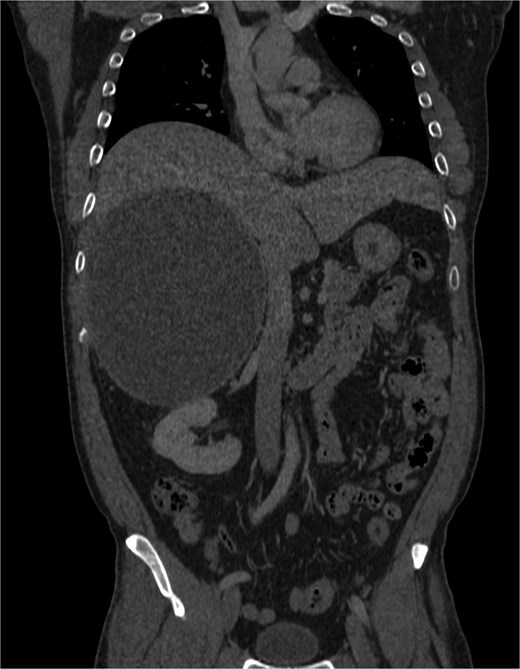

Positron-emission tomography (PET) scan with F18-Fluorodeoxy-glucose (FDG) and C11-Acetate, and combined contrast-enhanced computerized tomography (CT) revealed a predominantly cystic mass measuring ~14.8 × 17.9 × 18.6 cm located on the right side of the abdomen, arising from the retroperitoneal space with close approximation to the adrenal gland. It displaced the adjacent organs, including pancreas and the right kidney; A tiny mural calcification and focal hypermetabolic activity within the cyst wall raised the possibility of malignant transformation (Figs 1–4).

Cystic mass with mural calcification and tissue components in the posteroinferior portion, closely abutting the right kidney and adrenal.